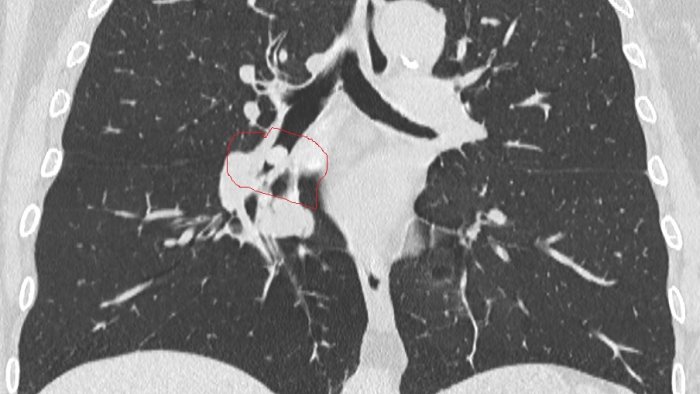

La donna, giunta al Pronto Soccorso con sintomi respiratori ad insorgenza acuta, insorti durante il pranzo, era stata rapidamente presa in carico dal personale dell’Emergenza-Urgenza e sottoposta dalla radiologa di turno, dott.ssa Chiara Ragone, ad esami radiologici, tra cui una TAC toracica.

Da tali esami è emersa un’ostruzione subtotale del bronco inferiore del polmone destro causata da sospetto corpo estraneo.

Prontamente trasferita in sala di Endoscopia Toracica, la paziente è stata sottoposta ad anestesia locale e, tramite videobroncoscopio flessibile, utilizzando una specifica pinza a cestello, le è stato rimosso il corpo estraneo, che è risultato essere un seme di cece che, inalato nelle vie aeree e che si era andato a conficcare nel bronco inferiore del polmone destro della donna, ostruendolo

totalmente.